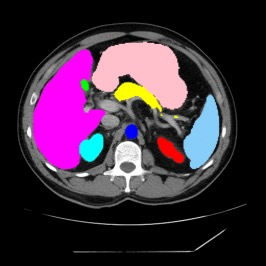

Integrating high-level semantically correlated contents and low-level anatomical features is of central importance in medical image segmentation. Towards this end, recent deep learning-based medical segmentation methods have shown great promise in better modeling such information. However, convolution operators for medical segmentation typically operate on regular grids, which inherently blur the high-frequency regions, i.e., boundary regions. In this work, we propose MORSE, a generic implicit neural rendering framework designed at an anatomical level to assist learning in medical image segmentation. Our method is motivated by the fact that implicit neural representation has been shown to be more effective in fitting complex signals and solving computer graphics problems than discrete grid-based representation. The core of our approach is to formulate medical image segmentation as a rendering problem in an end-to-end manner. Specifically, we continuously align the coarse segmentation prediction with the ambiguous coordinate-based point representations and aggregate these features to adaptively refine the boundary region. To parallelly optimize multi-scale pixel-level features, we leverage the idea from Mixture-of-Expert (MoE) to design and train our MORSE with a stochastic gating mechanism. Our experiments demonstrate that MORSE can work well with different medical segmentation backbones, consistently achieving competitive performance improvements in both 2D and 3D supervised medical segmentation methods. We also theoretically analyze the superiority of MORSE.

翻译:在医学图像分割中,整合高级语义相关的内容和低级解剖特征对于模拟这些信息非常重要。近期基于深度学习的医学分割方法已经显示出很有前景,可以更好地建模这些信息。然而,医学分割的卷积运算符通常在正则化网格上运作,这在本质上模糊了高频区域,即边界区域。我们在这项工作中提出了 MORSE,这是一个设计在解剖学水平上的通用隐式神经渲染框架,用于协助医学图像分割的学习。我们的方法的动机在于隐式神经表示已经被证明比离散化网格表示更有效地拟合复杂信号和解决计算机图形问题。我们方法的核心是将医学图像分割连续地对准粗糙的分割预测和模棱两可的基于坐标的点表示,并聚合这些特征来自适应地精细化边界区域。为了并行地优化多尺度像素级特征,我们借鉴了 Mixture-of-Expert (MoE) 的思想设计和训练我们的MORSE,使用随机门控机制。我们的实验表明MORSE可以很好地与不同的医学分割后骨干结合在一起,始终在2D和3D监督医学分割方法中实现了有竞争力的性能改进。我们还从理论上分析了MORSE的优越性。